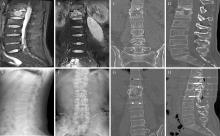

Objective: To investigate the effect of traditional Chinese medicine (TCM) syndrome differentiation and treatment combined with standard anti-tuberculosis regimen on postoperative rehabilitation in patients with spinal tuberculosis. Methods: One hundred sixty patients with spinal tuberculosis admitted to Shandong Public Health Clinical Center from January 2022 to January 2024 were selected and divided into an observation group (80 patients) and a control group (80 patients) using random number table method. Both groups underwent surgical debridement, bone grafting, fusion, and internal fixation for spinal tuberculosis lesions, along with the H-R-E-Z anti-tuberculosis regimen for 2 weeks preoperatively and 18 months postoperatively. The observation group additionally received TCM syndrome differentiation and treatment. Follow-up was conducted to record changes in clinical symptoms and signs, laboratory indicators, and imaging findings before and after treatment, then clinical effectiveness and occurrences of adverse reactions were compared between the two groups. Results: All patients were followed up for 18 months. The observation group had an earlier time to getting out of bed ((5.2±2.4) days) and a shorter hospital stay ((12.5±4.3) days) compared to the control group ((8.3±3.7) days and (16.4±5.6) days), with statistically significant differences (t=-6.29, P<0.001; t=-4.94, P<0.001). However, there was no statistically significant differences in treatment costs between the observation group and control group ((33607.5±8920.7) yuan vs. (36832.2±8763.1) yuan, t=1.91, P=0.058). Except for the erythrocyte sedimentation rate index 2 weeks after surgery, postoperative visual analogue scale, Oswestry disability index, erythrocyte sedimentation rate, and C-reactive protein scores at 1 week and 2 weeks were (4.23±1.12) score, (55.43±5.12) %, (45.03±15.76) mm/1 h, (33.74±10.19) mg/L, and (3.44±0.39) score, (32.14±6.25) %, (29.51±12.08) mm/1 h, and (17.43±8.37) mg/L, all better than the control group ((5.94±1.33) score, (68.15±6.93) %, (58.64±16.31) mm/1 h, (47.53±11.30) mg/L, (4.69±1.04) score, (43.35±7.15) %, (31.94±14.24) mm/1 h, and (23.25±9.56) mg/L), with statistically significant differences (t value were -8.81, -13.21, -5.37, -8.11, -10.08, -10.55, -1.16, -4.10,P value were <0.001, <0.001, <0.001, <0.001, <0.001, <0.001, 0.247, <0.001). At 18 months post-operation, no statistically significant differences were found in clinical cure rates between the observation group and control group (90.0% (72/80) vs. 85.0% (68/80), χ2=0.91, P=0.340). During the follow-up period, the recurrence rates in the observation group and the control group were 1.2% (1/80) vs. 5.0% (4/80), and the overall adverse reaction rates were 47.5% (38/80) vs. 65.0% (52/80), with statistically significant differences (χ2=3.88, P=0.049; χ2=5.33, P=0.021). Conclusion: Traditional Chinese medicine syndrome differentiation and treatment can promote early postoperative recovery in patients undergoing spinal tuberculosis surgery, lay foundation for long-term bone graft fusion, and simultaneously reduce recurrence rate and the incidence of treatment-related adverse reactions.